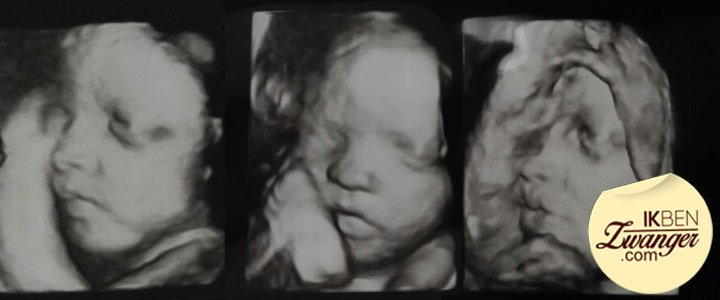

Een prachtig plaatje om van te genieten

De kleine lag met haar billetjes naar beneden en voetjes voor haar gezicht in een lenige positie. Zo schattig. Alleen om het gezichtje mooi in beeld te krijgen, was deze houding minder geschikt. Nu konden we alleen voetjes en handjes zien. Met paar keer draaien op mijn zij en het echo apparaat gereed kregen we uiteindelijk een prachtig plaatje te zien.

Neusje, mondje, oogjes. Een echt baby’tje in mijn buik. Dit meisje voelen we al weken lekker kriebelen en schoppen. Ze voelt zo dichtbij en nu hebben we er een foto bij. De echoscopiste kon zelfs zien dat onze dame al over heel wat haar beschikt. Een borsteltje kan meteen op onze baby benodigdheden lijst.